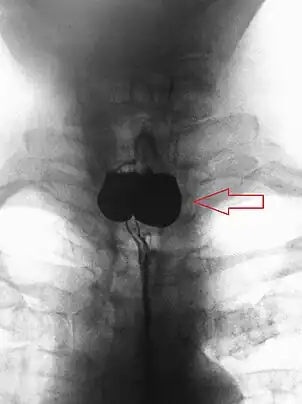

AP X-ray of a Zenker's diverticulum